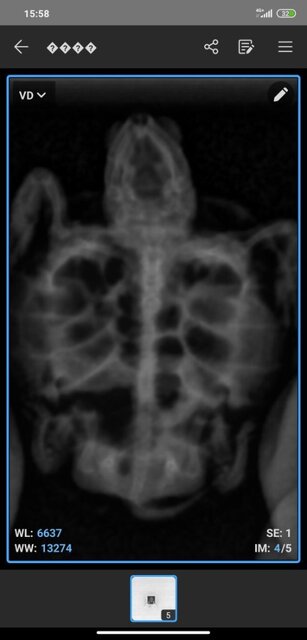

1760179420857.jpg

1760179420854.jpg

1760179420850.jpg

1760179420844.jpg

1760179381867.jpg